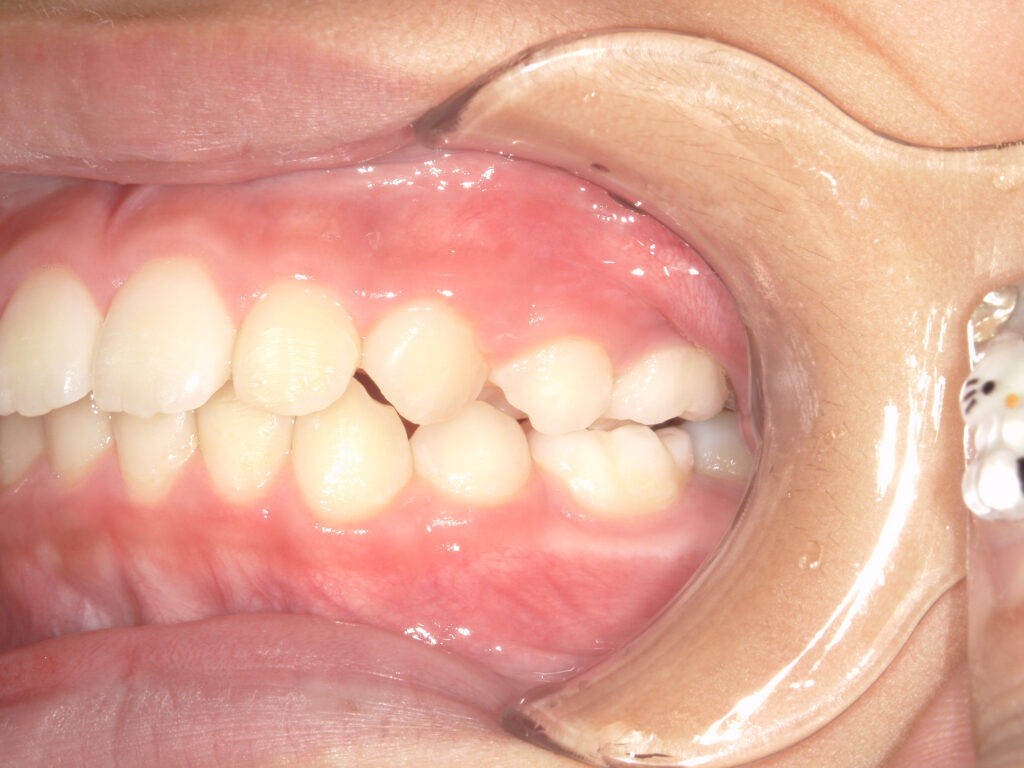

左側

治療後